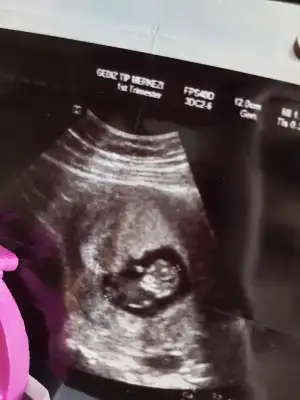

Cnm bu resimden bir şey anlayabiliyor musun ? Ikra meyra Ikra meyra

Eklentiler

• C8156FD9-B37C-4D1F-B618-5D7FABBBDEAA.webp

C8156FD9-B37C-4D1F-B618-5D7FABBBDEAA.webp

28,3 KB · Görüntüleme: 108

• 7E5CB6A4-1515-43F6-BD71-1DCDCDF0DA41.webp

7E5CB6A4-1515-43F6-BD71-1DCDCDF0DA41.webp

28 KB · Görüntüleme: 108